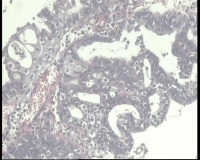

镜下见子宫内膜腺体异型增生,呈乳头状,筛网状排列,细胞核圆形,大小尚均匀,可见少量核分裂像,部分区域鳞化,间质少,部分区域无间质,间质有坏死

有些区域不能除外浆液性癌,最好做一做免疫组化协助鉴别。

浆液性癌!建议P53;P16'ER;PR等确认!